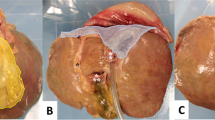

Installing and connecting porcine liver

The trainee removed the liver from the organ cluster and fixed the plastic connectors to the inside of the vessels. The trainee fixed the other point of the connectors to the inside of the corresponding tube. Finally, the trainee installed the liver (Fig. 3).

LC training procedures

The trainee could be trained in the major procedures of LC in this simulator, including: identifying, grasping, and retracting the gallbladder fundus, dissecting Calot’s Triangle, clipping the cystic duct and cystic artery, and removing the gallbladder (Fig. 4).